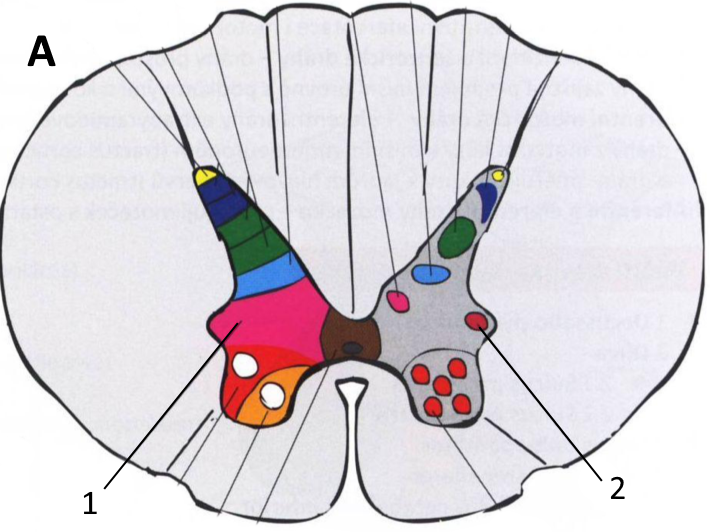

РОЗПІЗНАЙТЕ ОРГАНИ У ФРОНТАЛЬНІЙ ПЛОЩИНІ.

БОЛИТЬ НИЖНЯ КІНЦІВКА. ЧЕРЕЗ ЯКІ ОТВОРИ І ЯКОГО ВІДДІЛУ ХРЕБТА МОЖУТЬ ВИХОДИТИ НЕРВИ?

варіанти відповідей

ТОРАКАЛЬНОГО ВІДДІЛУ ХРЕБТА

ЦЕРВІКАЛЬНОГО ВІДДІЛУ ХРЕБТА

ЛЮМБАЛЬНОГО ВІДДІЛУ ХРЕБТА

ПОПЕРЕКОВОГО ВІДДІЛУ ХРЕБТА

КРИЖОВОГО ВІДДІЛУ ХРЕБТА

САКРАЛЬНОГО ВІДДІЛУ ХРЕБТА

МІЖХРЕБЦЕВІ БІЧНІ ОТВОРИ ХРЕБТА

МІЖХРЕБЦЕВІ БІЧНІ ОТВОРИ ХРЕБЦІВ